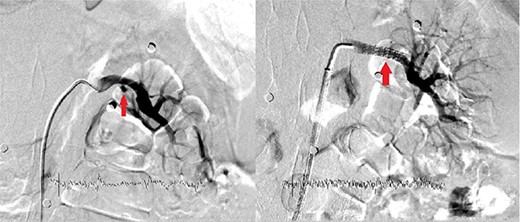

The patient was re-evaluated with CTA 3 weeks after discharge. Endovascular intervention was planned after observing that the left RAP was enlarged to 6 mm (Fig. 2). A renal angiogram was performed. After selectively catheterizing the left renal artery, a 6 × 3 mm filling extending inferiorly in the middle part of the left renal artery compatible with RAP was observed (Fig. 3). Following catheterization of the left renal artery with a long sheath, the lesion segment was passed with guide wire-catheter manipulations. Subsequently, a 6 × 22 mm covered stent (Advanta V12 Balloon Expandable Covered Stent, AMC, USA) was placed to include the RAP neck, and full expansion of the balloon and stent was achieved (Fig. 3). The control images revealed that the RAP was excluded from circulation, and the stent was patent. No embolism or bleeding was observed in the distal renal artery branches.

Tomographic angiography image of the enlarged renal pseudoaneurysm and the retained bullet core.